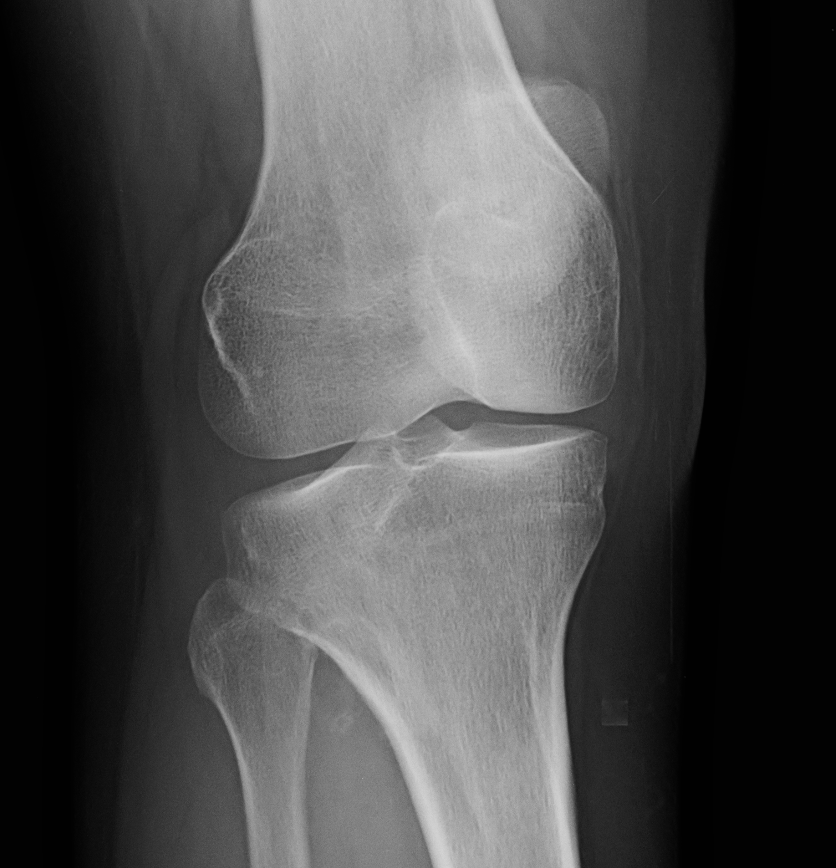

Рентгеновские снимки доброкачественных опухолей костей